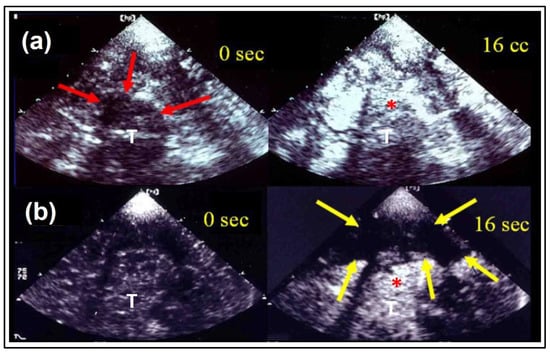

- Eyding, J.; Wilkening, W.; Reckhardt, M.; Schmid, G.; Meves, S.; Ermert, H.; Przuntek, H.; Postert, T. Contrast Burst Depletion Imaging (CODIM): A new imaging procedure and analysis method for semi-quantitative ultrasonic perfusion imaging. Stroke 2003, 34, 77–83. [Google Scholar] [CrossRef]

- Kern, R.; Perren, F.; Schoeneberger, K.; Gass, A.; Hennerici, M.; Meairs, S. Ultrasound microbubble destruction imaging in acute middle cerebral artey stroke. Stroke 2004, 35, 1665–1670. [Google Scholar] [CrossRef]